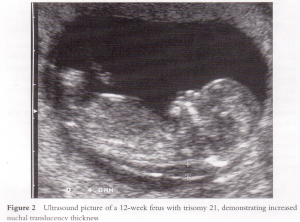

先天異常部より Nt Nuchal Translucency について 医療者向け 日本産婦人科医会

Nt Nuchal Translucency ある産婦人科医のひとりごと

14 初期の超音波マーカー検査 日本産婦人科医会

先天異常部より Nt Nuchal Translucency について 医療者向け 日本産婦人科医会

02 妊娠初期 胎児の頸部浮腫 Nt 妊娠11 13週でcheck 深谷産婦人科 医学情報

胎児超音波ーマーカー検査とは ヒロクリニック

ダウン症エコー写真 週目によるbpd Nt Flを解説 ダウン症ステーション

Nt 後頚部浮腫 とダウン症の関係 ままたまご日和 楽天ブログ

ダウン症nt検査とは何の事なのか ダウン症についてしっかり知ろう ダウン症の原因は

胎児の首の後ろのむくみ 浮腫 Nt とは 妊娠初期 All About

Nt Nuchal Translucency について 出生前検査 Nipt 遺伝カウンセリング 妊婦健診 エコー検査 産科 婦人科 産婦人科

胎児の首の後ろのむくみ 浮腫 Nt とは 妊娠初期 All About

ダウン症のエコー特徴 手足 頭 Bpd Nt Fl徹底解説 Down And Up